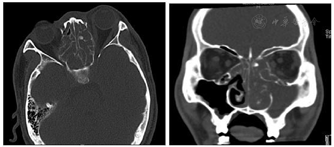

肺部CT见双肺上叶、右肺中叶多发散在结节状高密度影,边缘欠规则,密度均匀,大者位于右肺尖,大小约31mm×26mm,周围散在多发索条影及小结影,并见索条影牵拉胸膜。左下肺胸膜下小结节高密度影,边界清,气管及主支气管通畅,肺门、纵膈未见肿大淋巴结,胸腔内未见积液征。不除外真菌感染或结核(图3)。